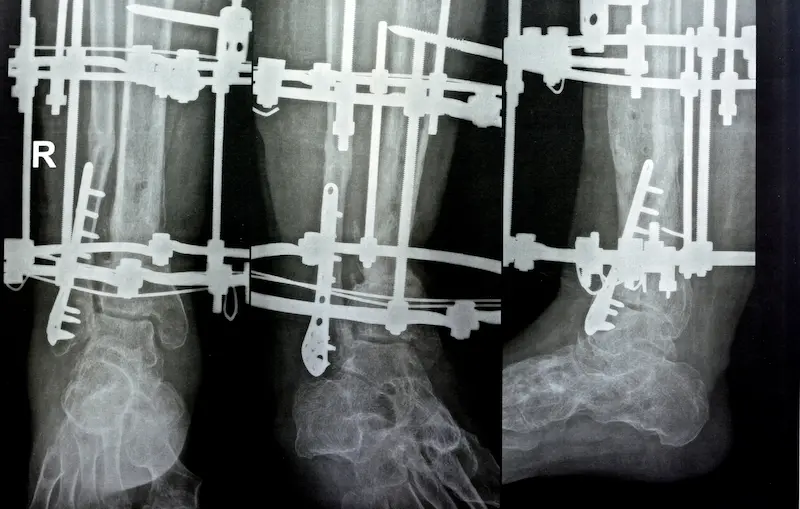

على الرغم من انتشار مصطلح “إطالة الأطراف”، تتعدد الطرائق والتقنيات المستخدمة وفقاً لقدرات كل مركز ورؤية كل جراح. ويعتبر جهاز إليزاروف من أكثر الطرق المعروفة عالمياً، لكن ظهرت في الأعوام الأخيرة ابتكارات متقدمة تتميز بحصر تدخل الطبيب وضبط الإطالة عبر أنظمة إلكترونية أو مغناطيسية.

المقدمة إلى تقنية إيلزاروف

تقنية إيلزاروف أقدم التقنيات وأكثرها استخدامًا حتى اليوم؛ اخترعها جرّاح روسي اسمه جافريل إليزاروف في خمسينيات القرن الماضي. ترتكز على مبدأ التثبيت الخارجي للعظام بهدف إحداث تباعد تدريجي بين القطع العظمية بعد كسر متعمد للعظم. يؤدي هذا التباعد (الإلهاء) إلى تحفيز نمو الخلايا العظمية، فيزداد طول الساق، ويمكن للمريض التحكم في معدل الإطالة عبر تدوير براغي صغيرة خارج الجهاز.

تستمد شهرتها من قدرة المريض على الحركة النسبية (مثل المشي بعكازات) حتى مع وجود الجهاز، إذ إن التثبيت خارجي وقوي، ولا يلزم المريض الفراش طويلاً.